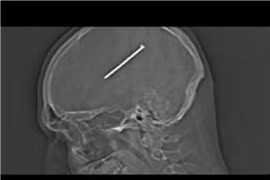

Sống với chiếc đinh dài gần 9 cm găm trong não